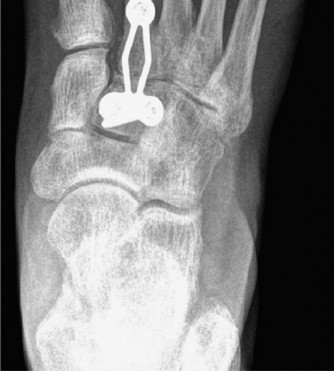

Fixation can be achieved using either solid compression screws or dorsal spanning plates.

* Screw Fixation: Traditional fixation utilizes 3.5mm or 4.0mm solid, fully threaded cortical screws placed in a lag fashion. A "home run" screw is often placed from the medial cuneiform into the base of the second metatarsal to recreate the Lisfranc ligament complex.

* Plate Fixation: Dorsal spanning plates have gained significant popularity, particularly in cases of poor bone quality or when avoiding articular surface violation is desired. Low-profile, pre-contoured locking plates provide rigid biomechanical stability and act as a tension band against the plantar-flexing forces of the forefoot.

Following final fixation, intra-operative fluoroscopy is utilized to confirm hardware placement, joint reduction, and the restoration of the osseous arches. The extensor retinaculum is meticulously repaired to prevent tendon bowstringing, and the skin is closed in a layered fashion.